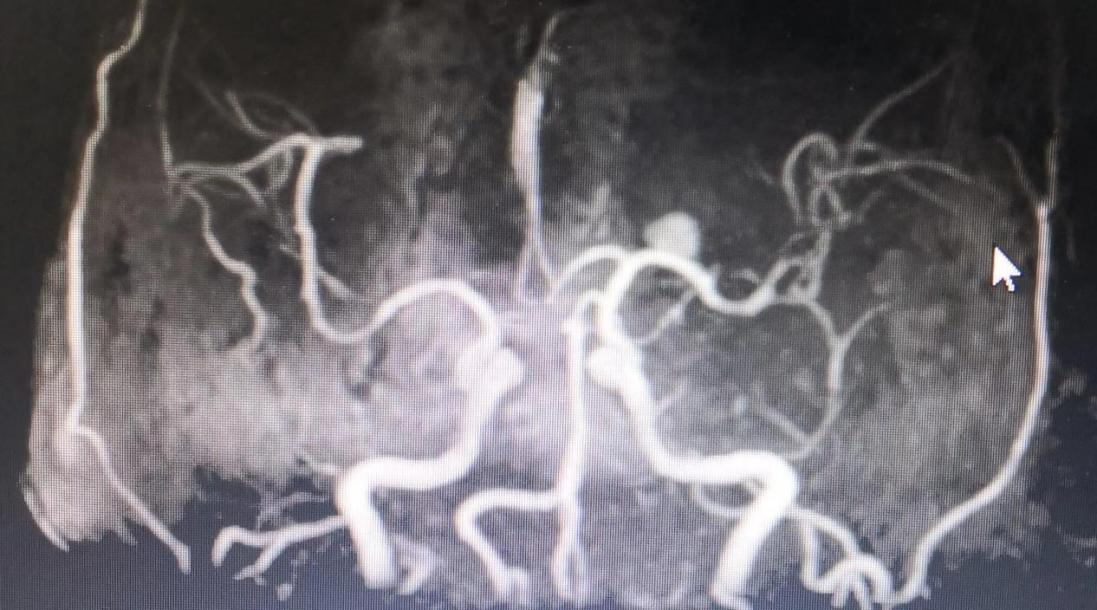

出院前复查头颅MRA脑血管无再闭塞